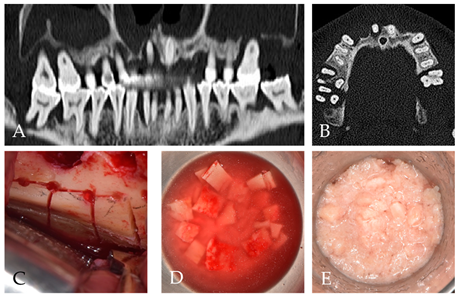

2. Case Report